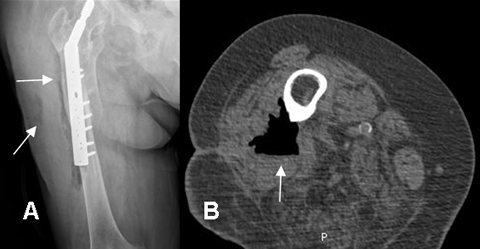

Fig 22. Absceso.

A: Rx AP. PostQx prótesis de cadera. Edema de tejidos blandos, con pérdida de los planos grasos. Se encuentra aire rodeando el hueso en la parte externa del muslo. (Flechas).

B: TAC axial. Formación de absceso con la presencia de nivel hidroaéreo. No se aprecia compromiso en la cortical del hueso.